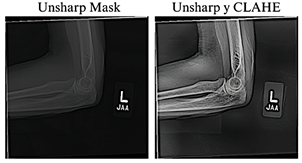

To improve the visual quality of the radiographs, the Unsharp Masking technique, used to emphasize edges and fine details [24], and CLAHE, which improves contrast in low-quality images without introducing unwanted artifacts [25], were applied.

Previous studies have shown that combining these techniques significantly enhances visibility in low-light images [26], as illustrated in Figure 2.

Figure 2. Application of radiographic image enhancement techniques. The image on the left shows the result obtained using Unsharp Mask, while the image on the right illustrates the effect of combining Unsharp Mask with CLAHE.